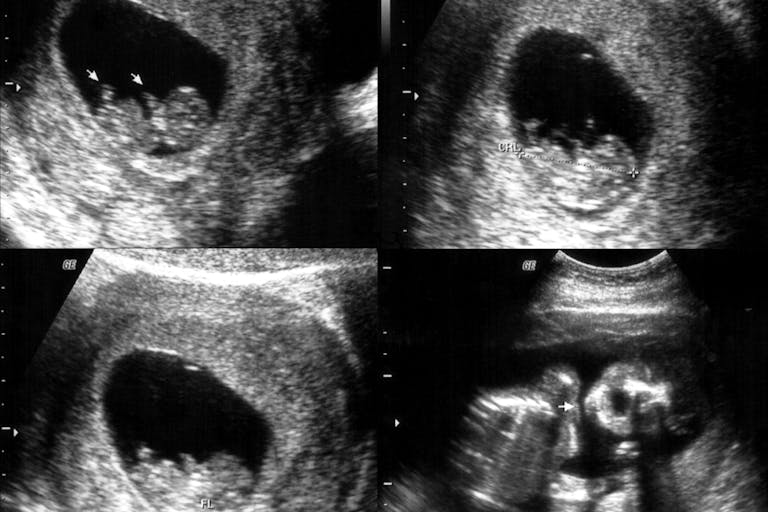

And although the AHCA did not find fetal parts sales, the unlicensed second trimester abortions, also known as dismemberment abortions, are troubling. The disturbing videos released included second trimester abortions, which is what the Houston video revealed with its dissection of the twin.